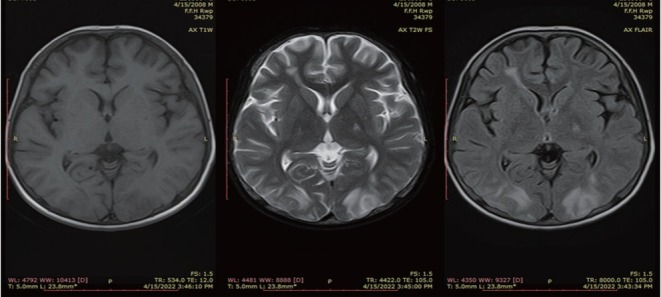

Magnetic resonance imaging (MRI) brain was requested considering the high index of suspicion for PRES. MRI showed hyperintense areas in bilateral occipito-parietal lobes as well as left capsuloganglionic regions (left thalamus) and left middle cerebellar peduncle on T2 weighted and fluid attenuated inversion recovery (FLAIR) sequences, which appeared isointense to hypointense on T1 weighted images (Figures 1 and 2). The occipitoparietal region showed diffusion restriction while rest of the areas showed T2 shine through on diffusion weighted images (Figure 3). A diagnosis of PRES supported by clinical features and radiological findings was made. He was managed in the intensive care unit with antihypertensives (intravenous [IV] labetolol) with an aim to reduce blood pressure by 25% in first 6 h. IV phenytoin was given to control seizures. The patient made an uneventful recovery within 2 weeks with no residual neurological deficit. Phenytoin was discontinued (fit free > 2 d) and rehabilitation was done.

Figure 1.

Axial T1WI, T2WI and FLAIR sequence showing areas of T2 and FLAIR hyperintensities in bilateral occipital lobes. T1WI, T1 weighted images; T2WI, T2 weighted images; FLAIR, fluid attenuated inversion recovery.